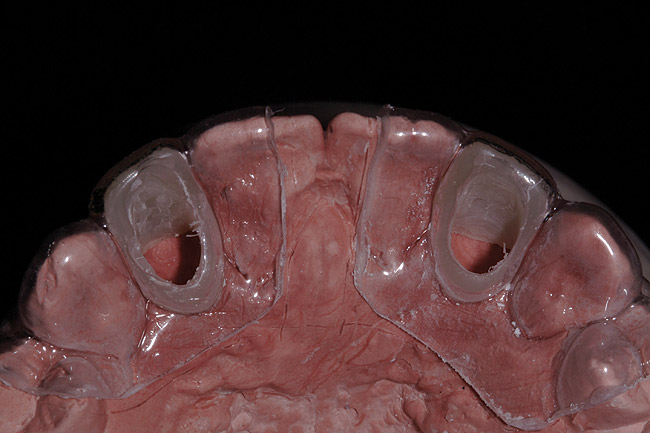

A 19-year-old non-smoking female presented for tooth replacement at the maxillary right and left lateral incisors, which were congenitally missing (Figure 1). The post-orthodontic result was adequate for the placement of 3-mm one-piece small-diameter implants. The preoperative radiographs can be seen in Figure 2 and Figure 3. The pretreatment clinical view in Figure 4 and Figure 5 shows the small intertooth space present in the lateral incisor areas. One of the most challenging tasks with congenitally missing lateral incisor cases is to create an acceptable soft tissue emergence profile from a crestal profile that is flat from the mesial of the canines to the distal of the centrals (Figure 4 and Figure 5). After pretreatment planning which consisted of a complete medical and dental history, radiographic analysis, and upper and lower study models mounted by a facebow transfer technique, the fabrication of a TempStent II surgical guide was completed. Figure 6 and Figure 7 show the occlusal view of the TempStent II guide on the study cast and in the oral cavity, respectively.

Figure 6  Occlusal view, TempStent II Surgical Guide.

Figure 6

Figure 7  Intraoral occlusal view, TempStent II Surgical Guide.

Figure 7